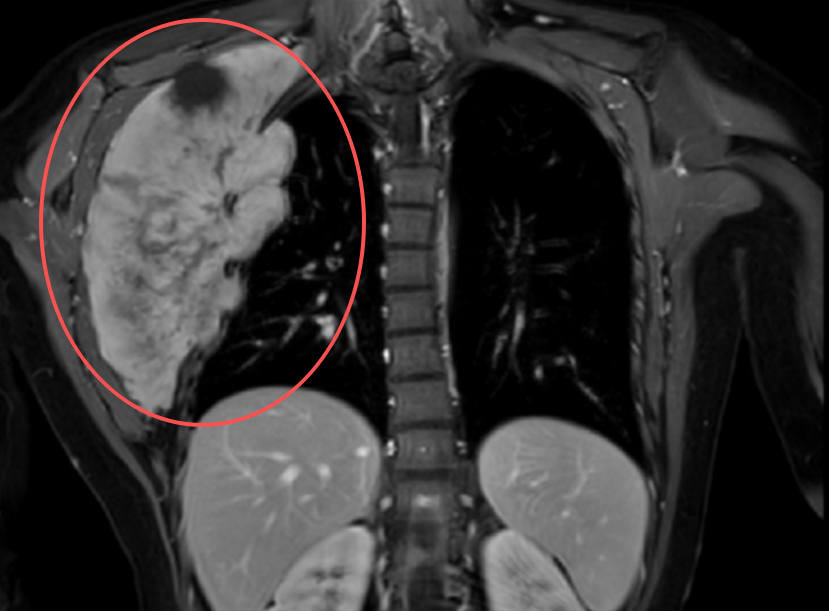

查看详情近日,真人电子网址胸外科林锋教授团队联合马林教授团队成功为一名21岁女性实施巨大胸壁肿瘤切除及胸壁重建手术,切除肿瘤约19×10×18cm,手术难度风险极大,涉及重要血管和神经结构...